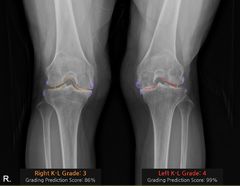

"무릎 악화 정도 한눈에"…10초만에 관절염 찾아내는 AI[빠정예진]

류난영기자2025.11.08 06:01:00